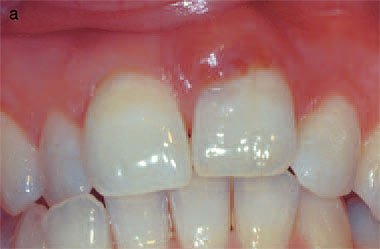

Fig. 4. (a) Labial view of the anterior teeth of a 28-yearold female who

had received fixed orthodontic treatment 14 years earlier. The maxillary

right incisor shows a pink discoloration near the gingivalmargin. (b) The

radiograph of the maxillary right incisor reveals an irregular radiolucency

overlying the root canal outline. From (20). Reproduced with permission

from Quintessence Publishing. |

Class 2

Invasive resorptive lesions of this class may present with a pink discoloration

of the tooth crown (Fig. 4a), while the radiographic image usually shows a surprisingly

extensive irregular radiolucency extending from the cervical area into the tooth

crown and projected over the root canal outline (Fig. 4b). If the lesion is proximally

located the radiographic image will show ar adiopaque line bordering the pulp

space. An examplec an be seen in a radiograph of the maxillary central

incisors of a 22-year-old male who had a history of extensive orthodontic treatment

in his teens (Fig. 5a).W hile this image is similar to that of dental caries,

it

differs in that the outline is slightly more irregular. The clinical appearance